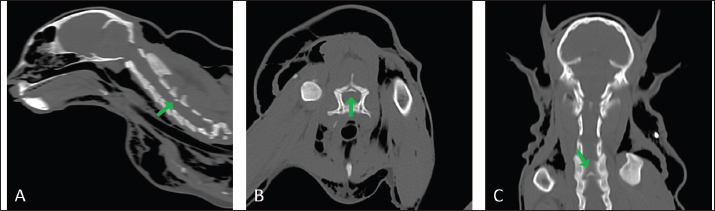

The cat was placed in sternal recumbency with the neck gently flexed in a neutral position. The skin was aseptically prepared, and a midline skin incision was made from the atlas to the level of the seventh cervical vertebra to explore the cervical region. The epaxial muscles showed evidence of blunt trauma without signs of direct laceration (Fig. 4A). The nuchal ligament was split longitudinally, and the cervical vertebrae spinous processes were identified. The multifidus muscle was elevated from the spinous processes to expose the dorsal lamina and perform the fourth and fifth cervical vertebrae skeletonization. The bone fracture was then identified at the dorsal lamina’s caudal margin of C4, caudal to the spinous process. The caudal fragment was grasped and elevated with bone forceps (Fig. 4B). The periosteum and ligamentum flavum lateral and caudal to the fragment were then severed and gently removed with a scalpel blade. The spinal cord below the fragment showed no gross alteration or signs of contusion (Fig. 4C). After removing the bone fragment, both fentanyl and ketamine CRIs were gradually tapered, and the cat remained normotensive with a normal heart rate until the end of the surgery. Once the surgical field was irrigated and adequate hemostasis was confirmed, the fascia, subcutaneous tissue, and skin were sutured in a routine fashion.

Fig. 4. Surgical approach to vertebral fracture of C4 through a dorsal cervical approach. (A) Once the surgical access was performed, the epaxial muscles showed gross evidence of blunt trauma (yellow dotted arrow). (B) The fourth and fifth cervical vertebrae were skeletonized to evidence the bone fracture. Then, the caudal fragment was grabbed, elevated, and removed, cutting the flavum ligament (note the bone fragment between the forceps, yellow dotted arrow). (C) The uncompressed spinal cord was visualized after the bone fragment was removed (yellow dotted arrow).